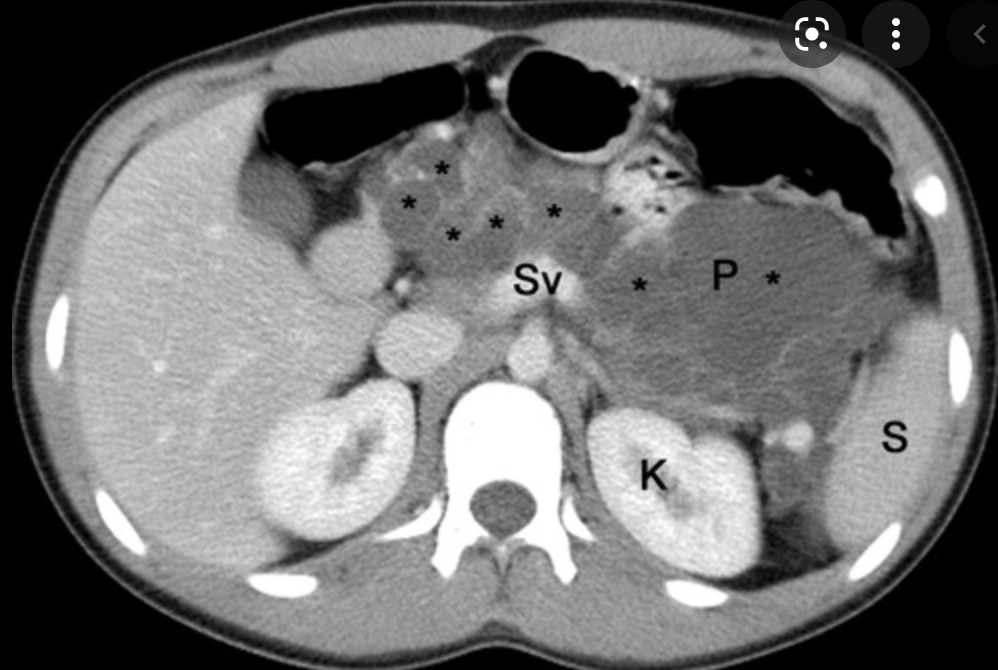

Single phase CT scan (multiphase scans not performed due to age of patient) demonstrates a diffusely enlarged pancreas with a “halo” like rim of hypoattenuating tissue which is smoothly marginated. Minimal peripancreatic fat stranding.

Associated splenic vein thrombosis, splenomegaly and cavernous transformation of the portal vein.